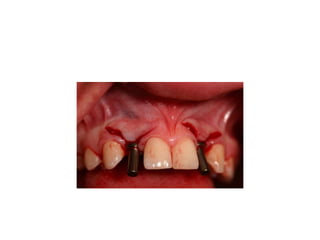

pre-op

palatal inflammation is noted from

retainer

implants are placed w/in restorative

confines